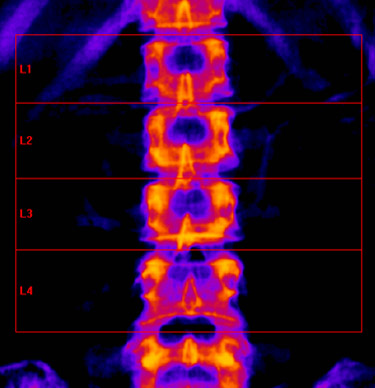

A free medical education seminar series for everyoneA FREE spine education seminar series for everyone Back pain has many faces and to many people it can be distressing, disabling or even frightening. Whether back pain comes from a strain, degenerative disc disease, a herniated disc, spinal stenosis, spondylolisthesis, a complex deformity or even a fracture, there are many options that can help you to live an active lifestyle. Additionally, osteoporosis is another disease that you may not even know you have. Learn from these dynamic experts about the various types of back problems and the latest treatments available. We will discuss the problems, the solutions and leave time for your questions to help you be active. Talk with the experts and get your concerns addressed. Spine Program